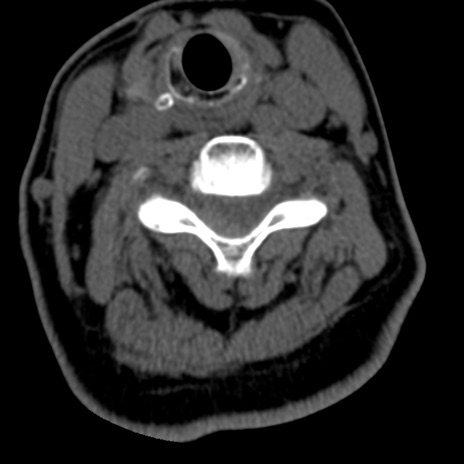

症例50 頚椎CT(横断像)

頚椎CT